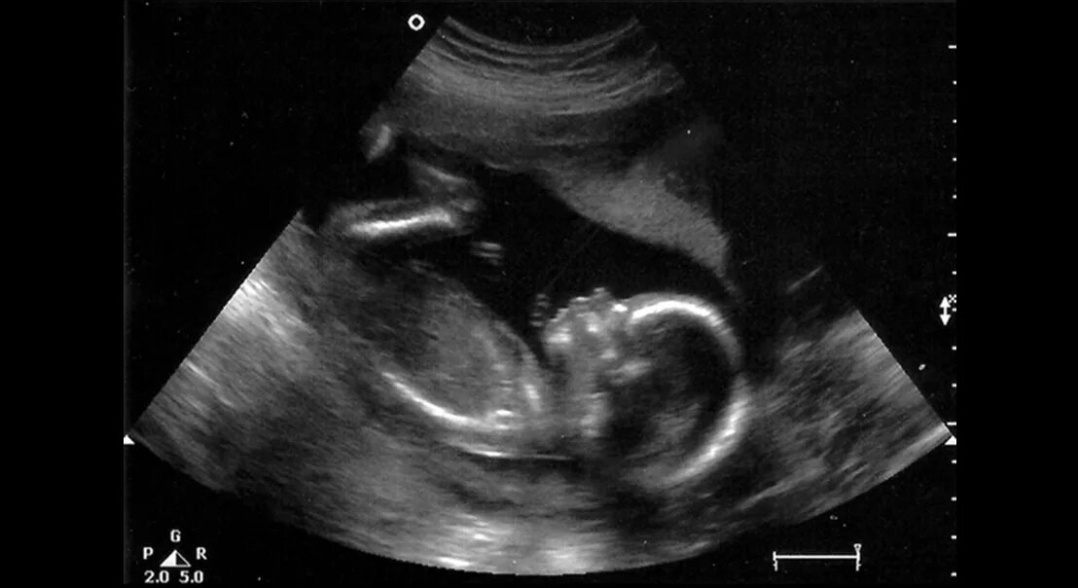

Я тогда работала еще только первый год. На прием пришла девочка-ангелочек. Ее ясные голубые глаза, фарфоровая кожа и нежные волны светлых волос сразу привлекали всеобщее внимание. Ей семнадцать. Она протягивает мне почему-то две карты. Я думала, что по ошибке. Оказалось, пациентка направлена гинекологом. Вторая карта - гинекологическая. Беременность 13 недель, затяжной кашель. После опроса и оформления первичной документации приступаю к осмотру. Сквозь медицинскую маску улавливаю тонкий аромат... сигарет. И у меня опускаются руки. В прямом смысле этого слова. "Ты куришь?"-спрашиваю я. Отвечает с улыбкой: "Да. Но немного. 5-6 сигарет в день" Моя фантазия моментально рисует перед взором маленького человечка, жаждущего жизни и любви, но вместо этого получающего отравленный дым и безразличие. Он сидит в этом лоне, как в тюрьме, пытаясь уловить свежий воздух и заботу, но лишен такой возможности. В его глазах немой вопрос: "За что, мама?" Он задыхается, плохо растет, тоже длительно кашляет

Спустя время я встретила ее в очереди на втором неонатальном скрининге. Поскольку у нас одинаковый срок, неудивительно, что мы столкнулись именно там. Но, когда она выходила от врача с заключением, то уже не улыбалась. Наоборот была сильно обеспокоена, нахмурена и даже нервничала. Я хотела спросить, все ли хорошо, однако она меня не заметила, а я постеснялась. Все таки лечить и учить без запроса нельзя. Позже я узнала: на этом самом скрининге было выяснено, что у ее плода идет задержка развития на 2-3 недели положеного срока. У юной матери раскрытие внутреннего зева на 1,5 см. Она едет домой, трясется 3 часа на общественном транспорте. На следующий день ее экстренно направляют обратно, снова 3 часа езды. Доезжает до приемного покоя Республиканской больницы и пока ждет очереди к врачу, у нее случается самопроизвольный выкидыш на 20 недели беременности. Спасти ребенка не удалось. Плод на этом сроке нежизнеспособен.